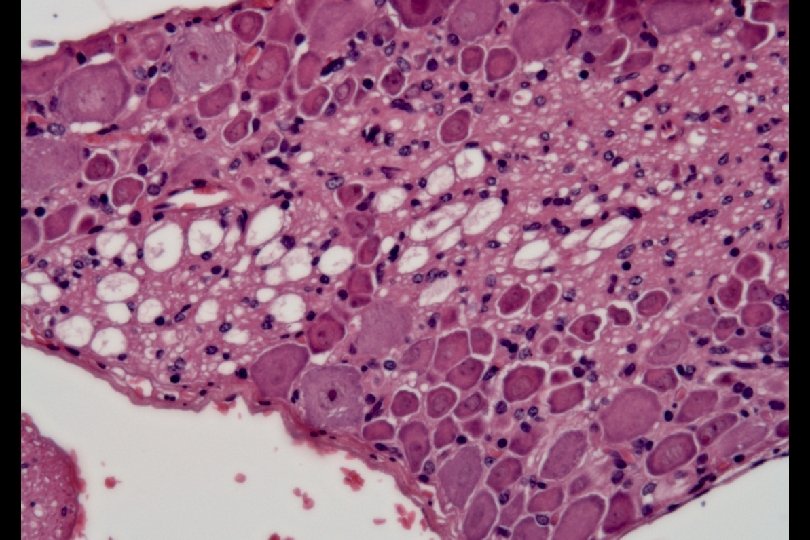

ENU-mutagenized mice displaying waddling behavior were linked to Chr. 18 151 M B 6, ♂ waddling (video) Normal BALB, ♀ BALB F 1 (video) Dominant Inheritance F 2 (video) Rough mapping Psy. Lab 2006 Dec

Four of five (80%) waddling mother mice did not nurse their pups The only one nursing mother killed all of her five pups at age 2 weeks.

Functional and Micro-Magnetic Resonance Imaging Center DWI_SE_BIO waddling control Lt Entorhinal cortex Lat ventricle TR=1500 ms TE=32 ms Slth=1 mm FOV=2 cm NEX=4 SW=41666. 6 Hz Big delta=15 ms Matrix =256*192 b=1100 s/mm 2

Functional and Micro-Magnetic Resonance Imaging Center DWI_SE_BIO waddling control Lat ventricle TR=1500 ms TE=32 ms Slth=1 mm FOV=2 cm NEX=4 SW=41666. 6 Hz Big delta=15 ms Matrix =256*192 b=1100 s/mm 2